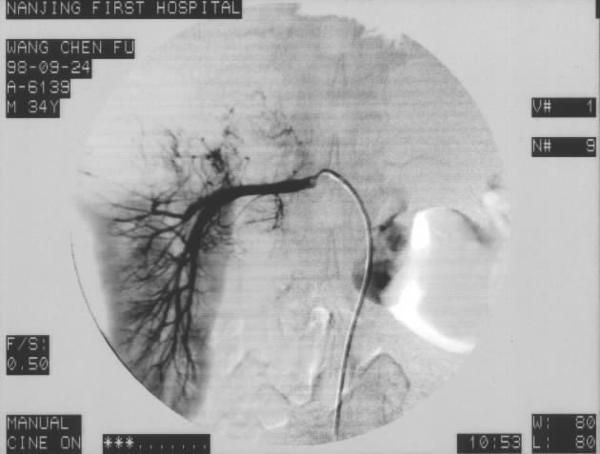

肾癌的诊断主要依靠临床表现及相关检查。典型三大症状都出现时已是晚期。X线平片诊断价值不大;在肿瘤侵犯肾盏肾盂后,静脉肾盂造影可以显示肾盏肾盂受压侵蚀所产生的变形、扩张积水等改变。二维超声目前已成为诊断肾癌的常用检查方法,超声鉴别肾囊肿与肾实质性肿块准确性可达90%~95%。CT是诊断肾癌不可缺少的手段,可显示肾癌的大小、部位、侵犯范围和有无淋巴结肿大、静脉内癌栓及邻近器官的转移等。MRI在诊断肾癌和对其正确分期中的一个重要作用是显示肾静脉和下腔静脉癌栓。MRI对于了解肾癌与周围器官和结构的关系也有较大的帮助,可以从不同的平面来观察肾癌是否已经侵犯了周围的器官和结构。肾动脉造影是诊断肾脏肿瘤性疾病的重要方法,成为介入放射诊断治疗中的重要环节。腹主动脉造影及选择性肾动脉造影可为选择治疗方案提供资料并为介入治疗提供指导。

通常采用股动脉穿刺作腹主动脉造影或选择性肾动脉造影,在观察血管造影表现后,对肿瘤相关血管作选择性与超选择性灌注化疗药物和栓塞。栓塞可分为永久性或暂时性、完全性或不完全性。常用栓塞剂包括:无水酒精、明胶海绵、中药白芨粉、钢圈及碘油+抗癌药等。